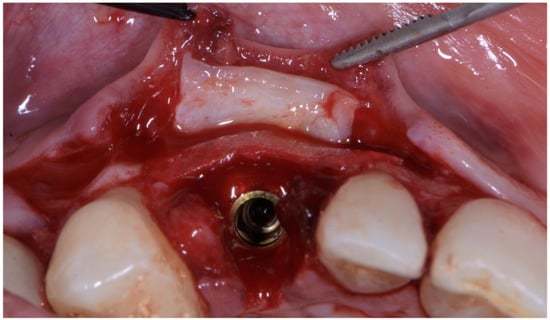

The implant site was prepared in a fully guided manner, using drills of progressively larger diameter, so that at the moment of guided implant insertion, the fixture could reach the pre-established position with enough primary stability to consent immediate provisionalization (35 Ncm) (Figure 6a,b). The implant shoulder should be palatal with respect to the imaginary line that connects the buccal profile of the adjacent teeth without placing it so that it is excessively palatal, in order to avoid creating prosthetic emergence profiles that are too horizontal, which are difficult to maintain in terms of hygiene.

Figure 6. (a,b) Implant placement after guided preparation of implant site.